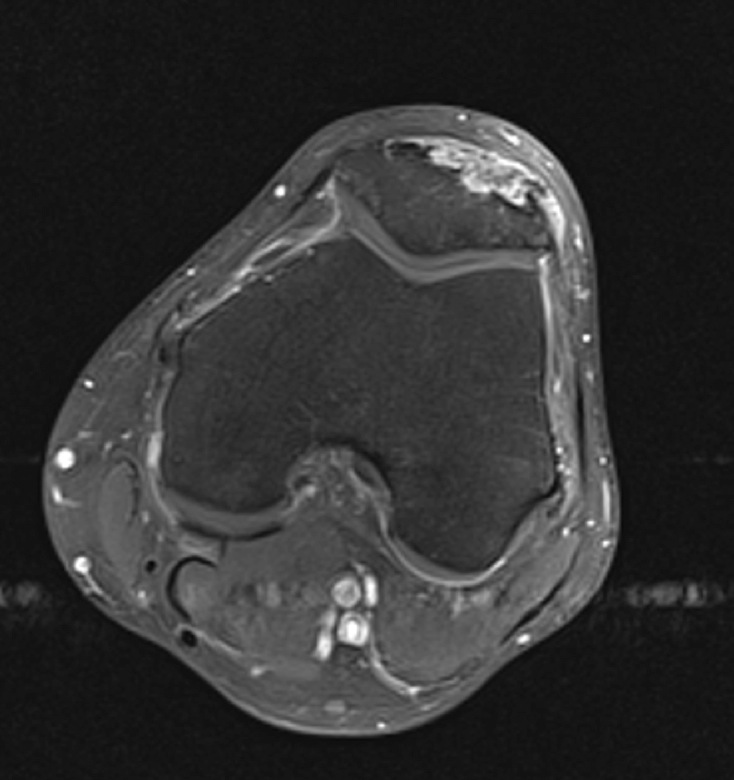

Figure 2 for case gout arthritis ( RID3567 )

Figure 2